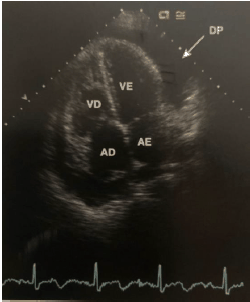

A imagem ecocardiográfica abaixo pode evoluir para uma emergência cardiológica que pode ter consequências graves, incluindo a morte. Baseado na figura abaixo, assinale a alternativa correta.

Provas